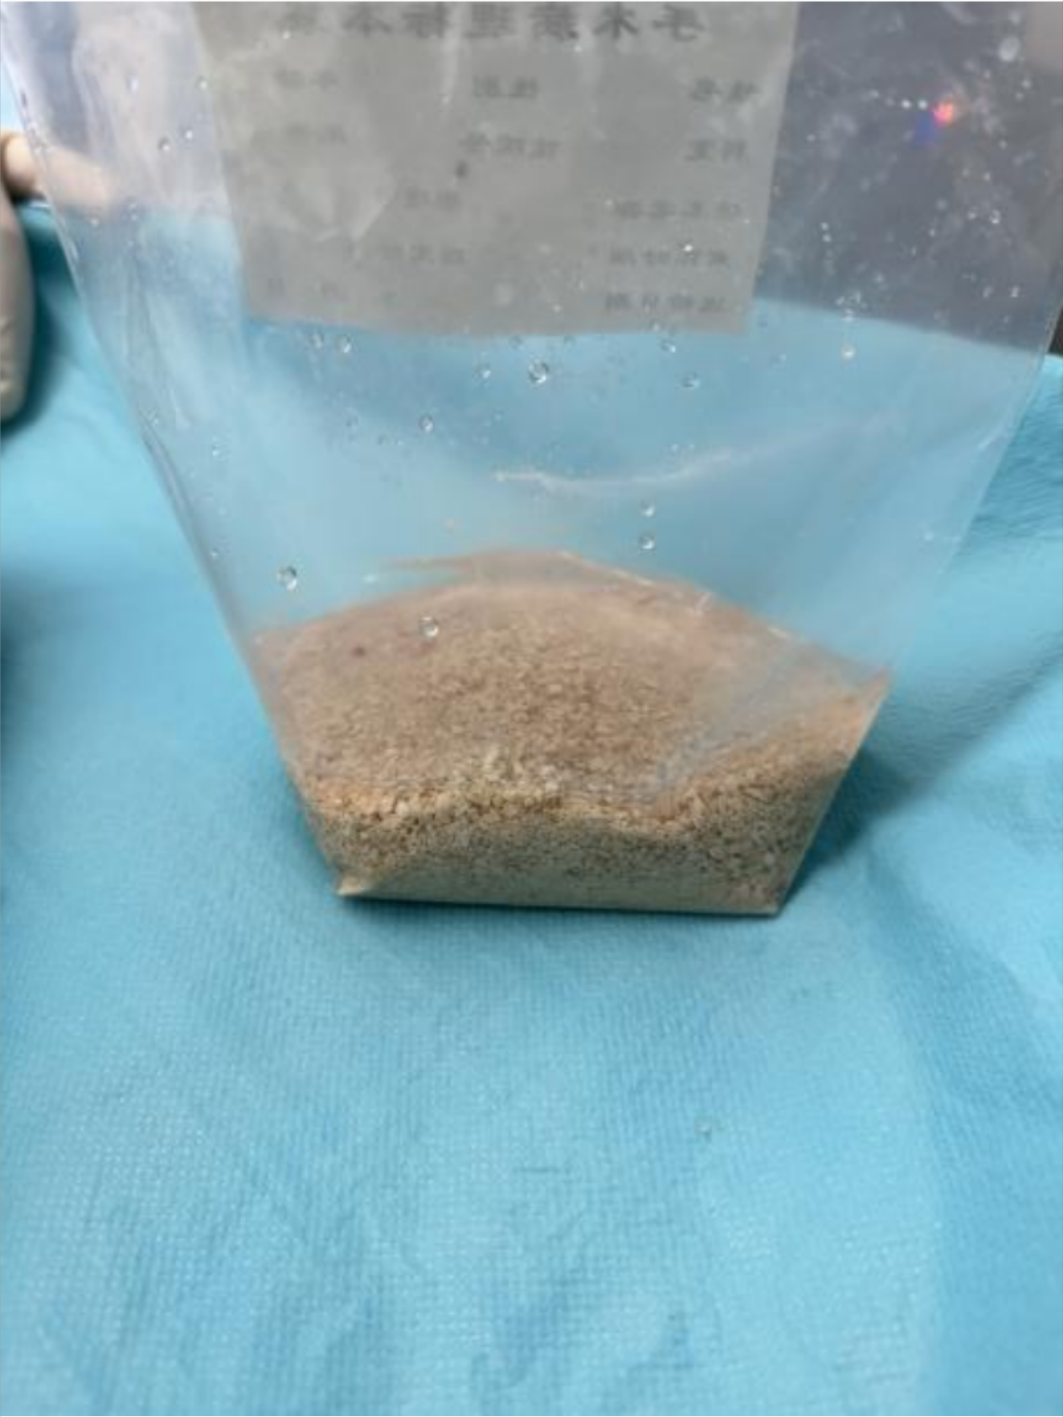

结石粉末话后完全取出